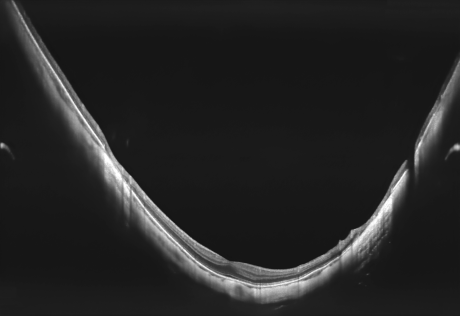

Full Range-Aufnahmen

Das Extended Depth Retina Imaging, welches auf der Full Range-Technologie basiert, bietet Scans mit größerer Tiefe für eine zuverlässige und bequeme Kontrolle von schwierigen Fällen. Dank der Scans mit großer Tiefe ist dieser neue Bildgebungsmodus perfekt für die Diagnose von sehr stark kurzsichtigen Patienten geeignet. Außerdem bietet sie einen Überblick über die gesamte Vorderkammer, von Hornhaut bis zur Augenlinse.

- Darstellung des vollständigen vorderen Systems

- Messung beider Kammerwinkel in einer Aufnahme

- Automatische Pachymetrie

- Analyse des Kammerwinkels

- Darstellung der Iris

Zusätzlich existiert ein Scan-Programm zur detaillierten Darstellung der Vorderkammer.